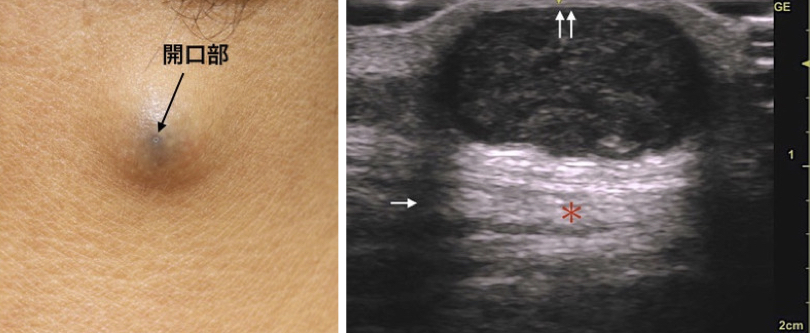

今回の症例も頚部の粉瘤腫で、くりぬき法を行います。

いつものように、くり抜き法で20分以内に終了するぞ!と思いきや、今回はやや慎重にならざるおえません

なぜなら恐怖のErb's pointが近くにあるからです

消毒&局所麻酔後に、いつものように4mmトレパンで穴をあけます。

腫瘍の袋も絞り出されました。できるだけまわりの組織に触れないように袋を取り出します。慎重に!

最後は縫合して軟膏をぬって終了です。縫わなくてもいいんですが、今回も縫った方がきれいになりそうで縫いました。腕の麻痺が無いかチェックすることも大切です。でも、結局15分程度で終わっちゃいました![]()